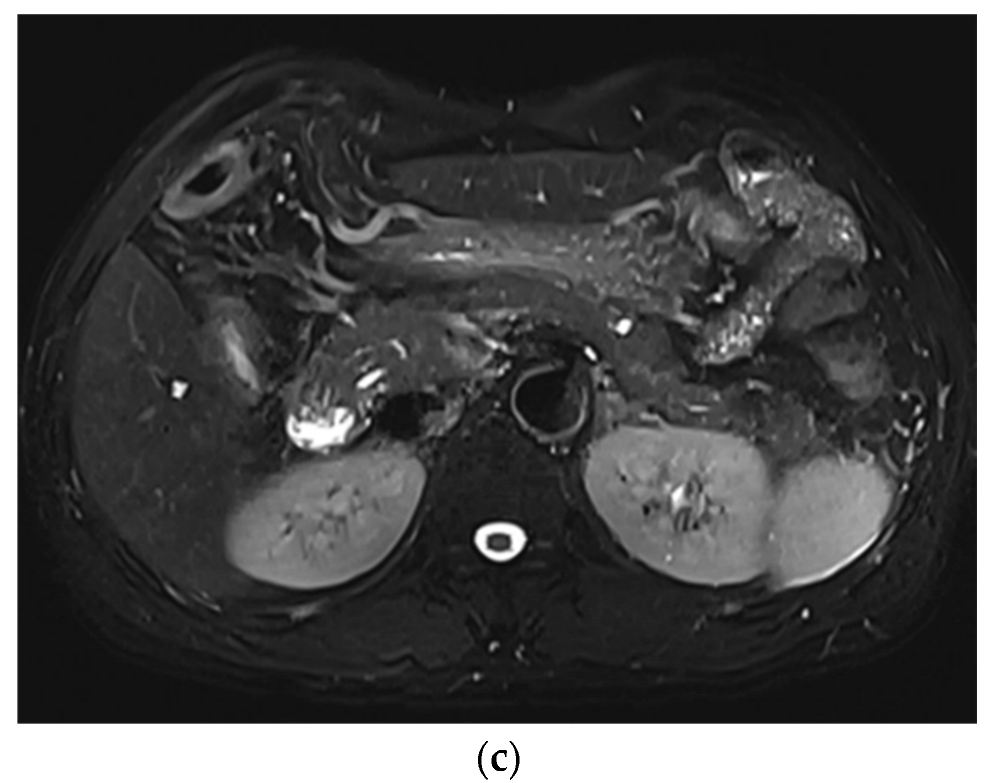

Improved Single Breath-Hold SSFSE Sequence for Liver MRI Based on Compressed Sensing: Evaluation of Image Quality Compared with Conventional T2-Weighted Sequences

3. Results

3.1. Subjective Image Quality

3.2. Lesion Assessment

4. Discussion